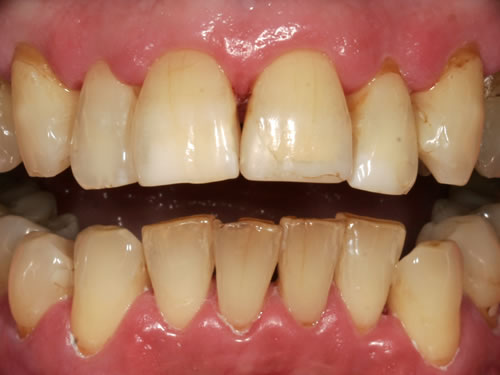

In den meisten Fällen ist nach der Untersuchung und Planung noch eine Vorbehandlung notwendig. Zunächst wird routinemäßig eine professionelle Zahnreinigung durchgeführt, um die Keimzahl in der Mundhöhle und in den Zahnfleischtaschen zu reduzieren (Abb. 5.11, 5.12). Anschließend sollten alle kranken Zähne, entzündetes Zahnfleisch oder auch Kiefergelenkerkrankungen behandelt werden. Die Planung der Einpflanzung sollte immer unter dem Gesichtspunkt der Sanierung des gesamten Gebisses erfolgen. Sie umfasst die Auswahl der geeigneten Implantate, ihre Anzahl und die genaue Position. Diese Vorbereitungen sind sehr wichtig, um nach der Einheilungszeit einen Zahnersatz anfertigen zu können, der die Wiederherstellung der Funktion und der Ästhetik gewährleistet.

Abb. 5.11: Zustand vor professioneller Zahnreinigung.